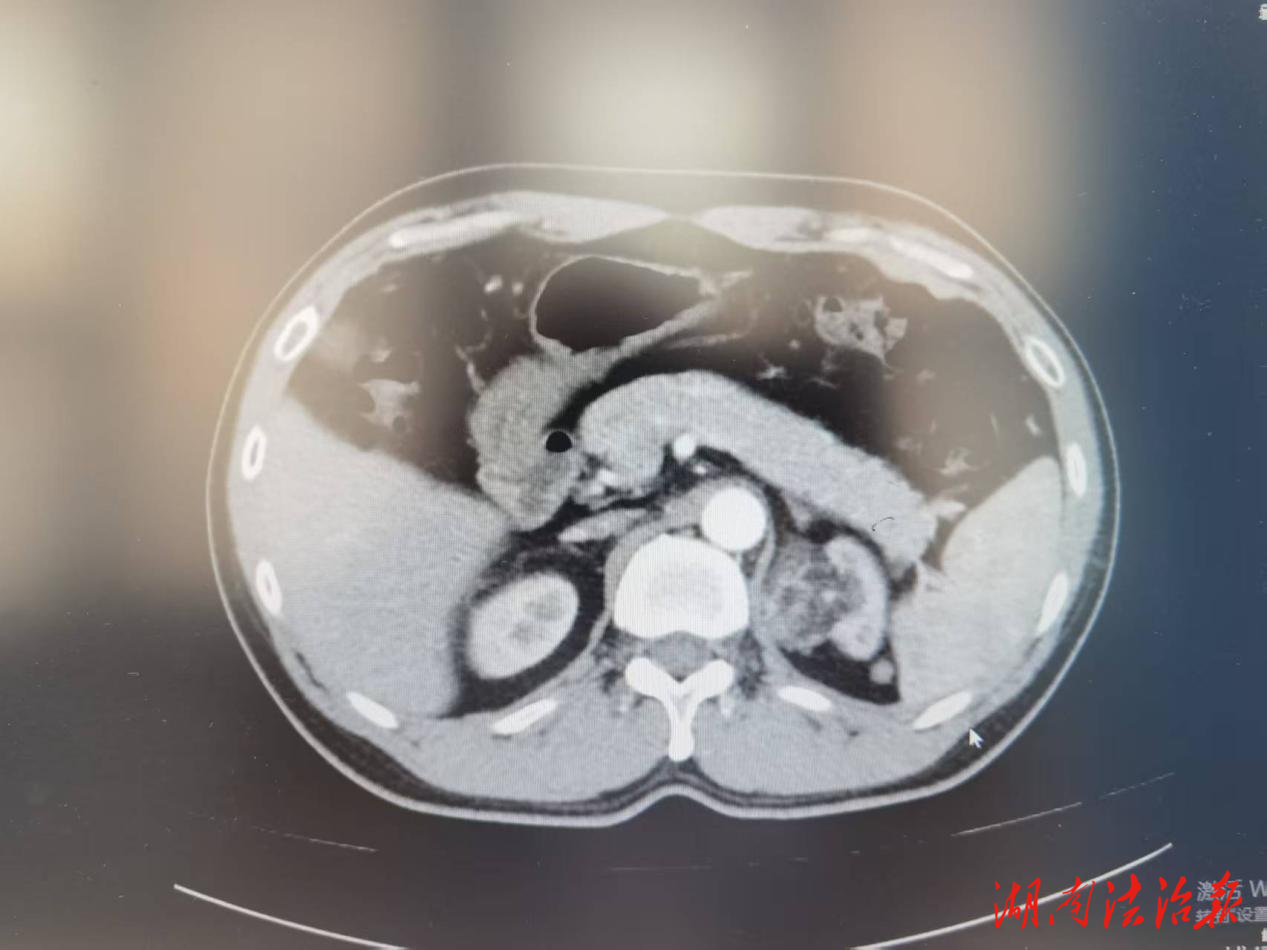

患者男,42岁,因发现“左肾包块13天”前往新田县中医医院外一科(泌尿外科)就诊。经腹部增强CT检查,明确诊断为左肾错构瘤。泌尿外科团队结合患者病情、身体状况,经全面术前评估和充分术前准备,于 4 月 22 日在全麻下为患者顺利实施了肾动脉阻断下腹腔镜左肾部分切除术,在完整切除肾脏肿瘤的同时,最大限度保留患者正常肾单位,最大程度保护肾功能。相较于传统开放手术,该微创手术具有创伤小、出血少、术后疼痛轻、恢复快等显著优势。此例手术的成功开展,填补了该县肾错构瘤微创保肾手术的技术空白。

患者男,76岁,因“无痛性血尿1天”紧急入院,经腹部增强CT及多次尿脱落细胞学等专项检查,确诊为右肾盂癌。该患者病情复杂,同时合并冠心病、房颤、心功能评定为NYHA分级二级,身体基础条件差,手术麻醉风险、术中、术后并发症风险远高于普通患者,手术难度极大。